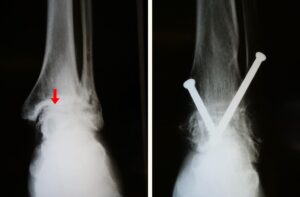

(Left) X-rays show ankle arthritis. Joint spacing narrow (arrow) has resulted in bone rubbing on bone. (Right) A different arthritic ankle after treatment with arthrodesis. Screws are used to hold the bones in proper alignment until the fusion is complete.